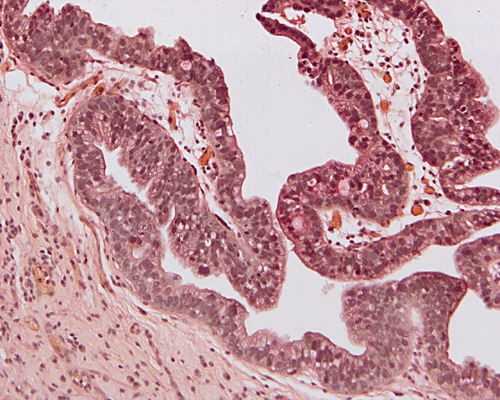

On scanning-magnification, the biopsy material consists of small nodules of stromal tissue with epithelium lined papillae (Panel A). On low-magnification (Panel B), both multilayered epithelium  and cribiform pattern (Panel C)are demonstrated. On high-magnification  (Panel D), the epithelial cells are hyperchromatic and pleomorphic. Intracytoplasmic mucin is well demonstrated by periodic acid-Schiff (PAS)- Alcian blue stain (Panel E) and mucicarmine stain (Panel F). No invasion is demontsrated.

PAS-Alcian blue

Mucicarmine